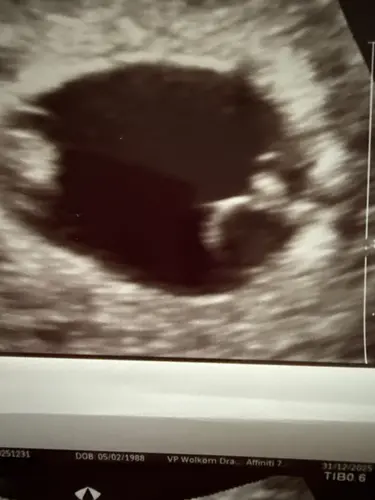

Is er iemand die dit mee gemaakt heeft ik ben 6 weken en 3 dagen zwanger is gemeente op de echo en het zijn er 2 maar bij kindje 1 geen kloppend hart te zien bij kindje 2 wel kindje 1 licht de dooierzak voor en kindje 2 achter heeft iemand dit ook meegemaakt kan het hartje van kindje 2 nog gaan kloppen ze leven samen in 1 vruchtzak